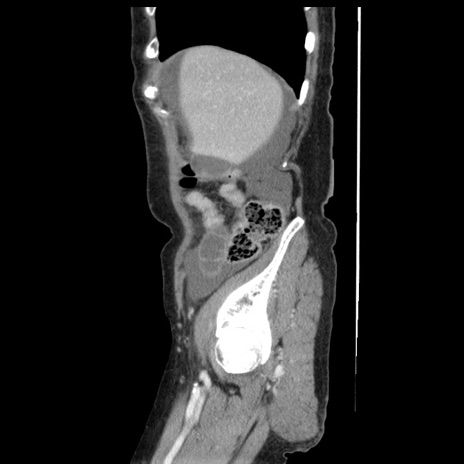

症例1(矢状断像)

【症例】80歳代女性

【主訴】腹痛

【現病歴】8時間前から腹痛あり来院。

【既往歴】糖尿病、脂質異常症、子宮体癌にて子宮全摘術

【身体所見】意識清明・会話良好だが腹痛で苦悶様、全腹部にわたって反跳痛と圧痛あり

【データ】WBC 13600、CRP 0.14、LDH 224、CK 90